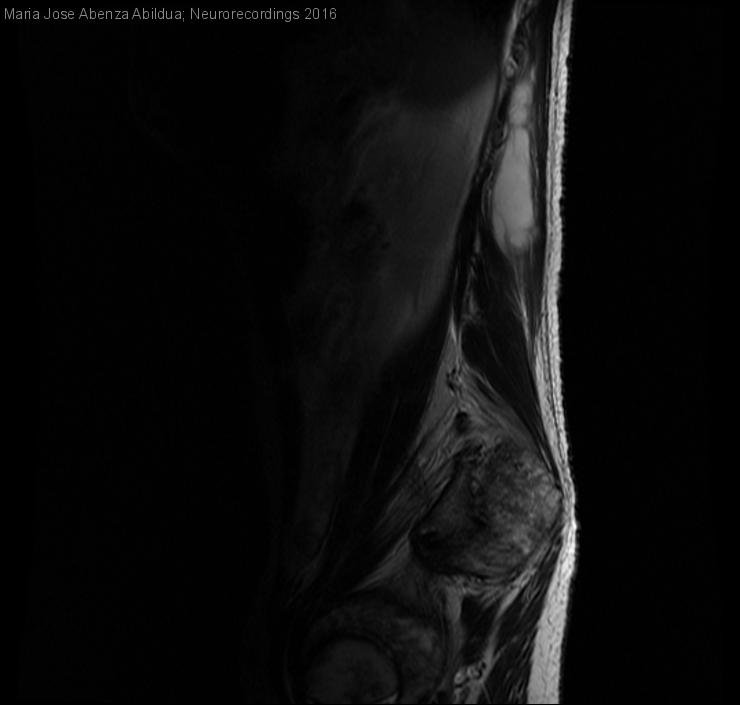

Hombre | 58 años

Diagnóstico final: Abcesos musculatura paravertebral lumbar